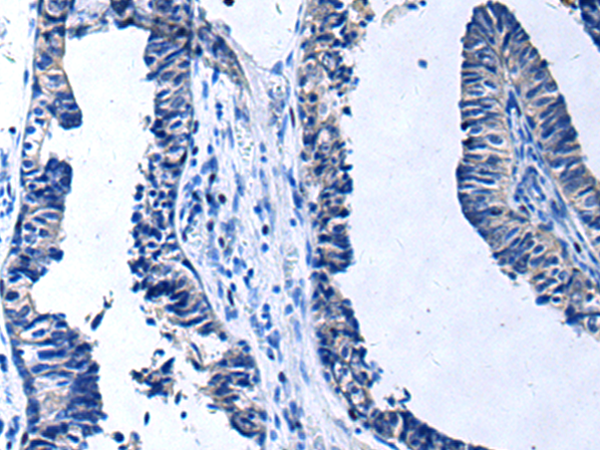

分类: 科研抗体货号: P06442别名: IL-34; C16orf77应用: WB,IHC反应种属: Human